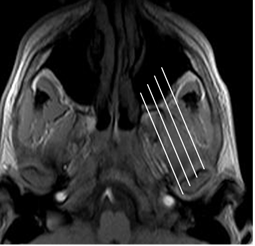

El estudio de la ATM con RM, debe incluir cortes sagitales oblicuos (Fig 4) y protecciones dinámicas, con boca abierta y boca cerrada. Las secuencias en gradiente de eco (GE), permite identificar mejor la posición y características del disco. (2).

Fig 4.Orientación de los cortes sagitales oblicuos en RM.